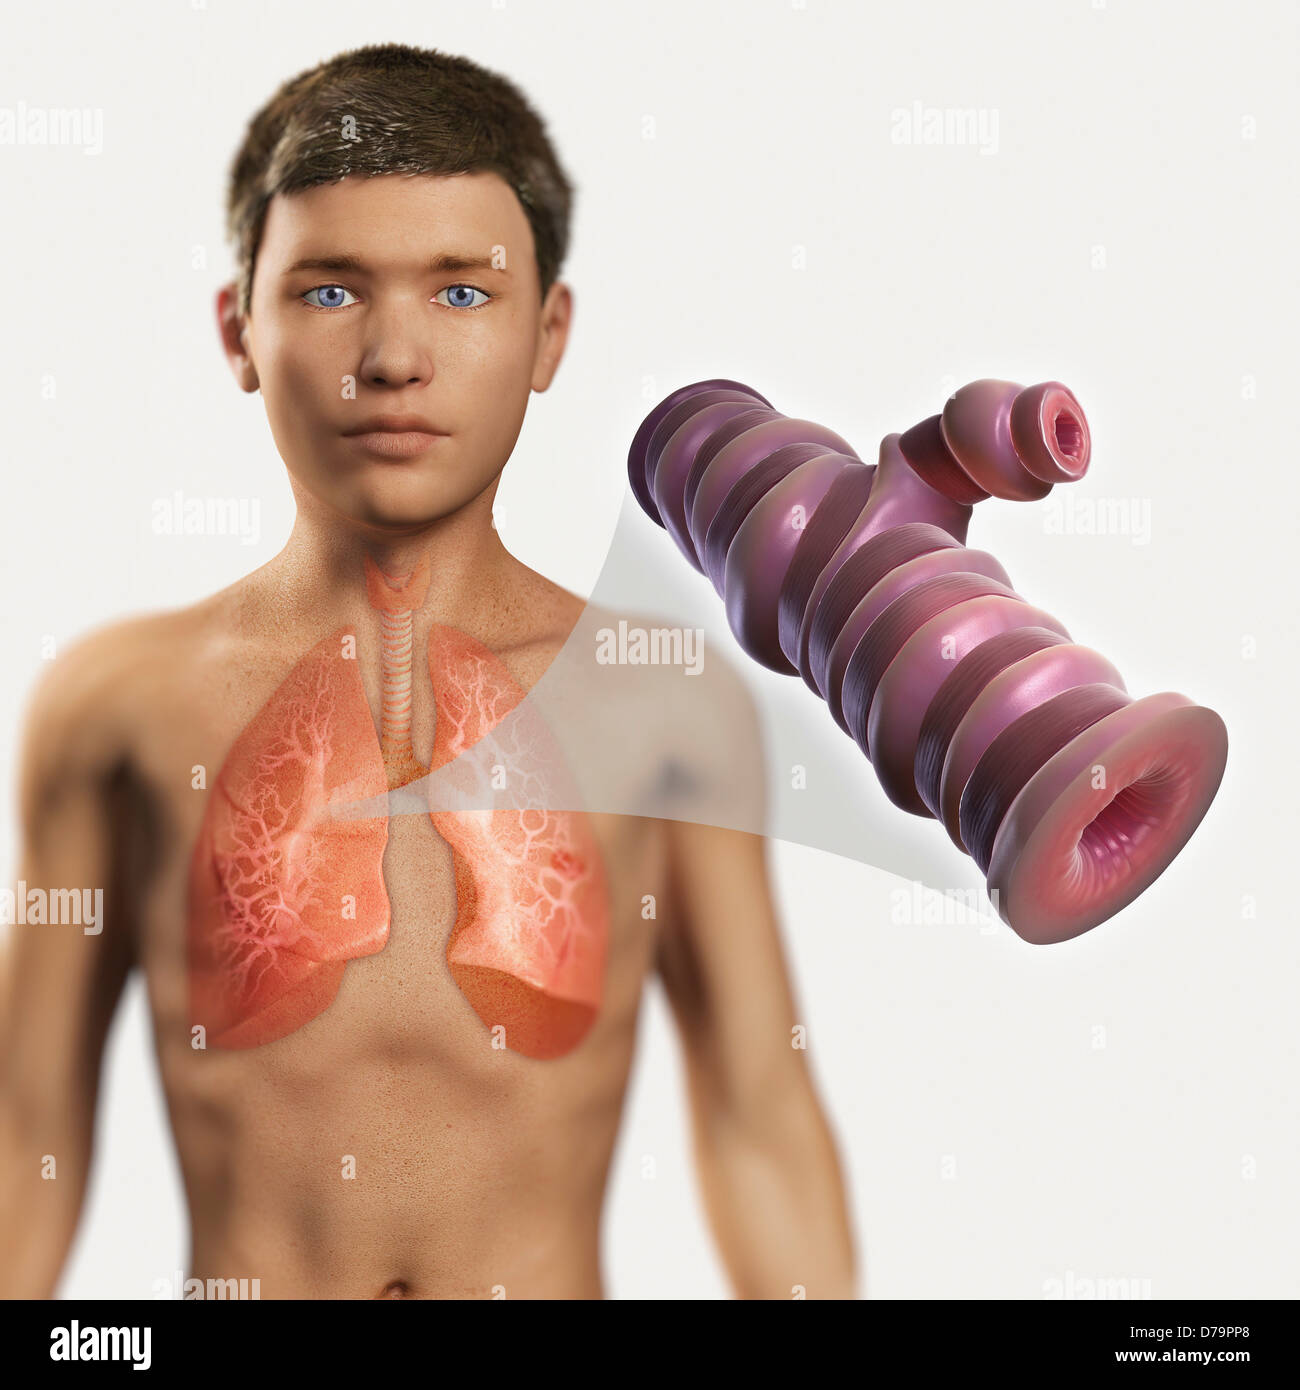

RF2R9D0YJ–Human trachea airway tube medical diagram icon

RF2RD0XXC–Human trachea airway tube medical diagram icon